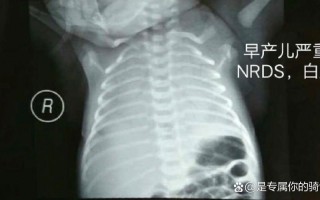

新生儿健康护理 新生儿照X光会影响健康吗? 这是一个非常常见且重要的问题,新手父母有这个顾虑非常正常,我们来详细、科学地解答一下,核心结论:对于医生认为有必要的检查,新生儿做X光检查的益处远大于其微小的、可控的风险,现代医学的X光检查技术已经非... 99ANYc3cd6 2025-11-30 0 #新生儿照X光辐射风险 #婴儿X光检查安全影响 #新生儿X光健康危害